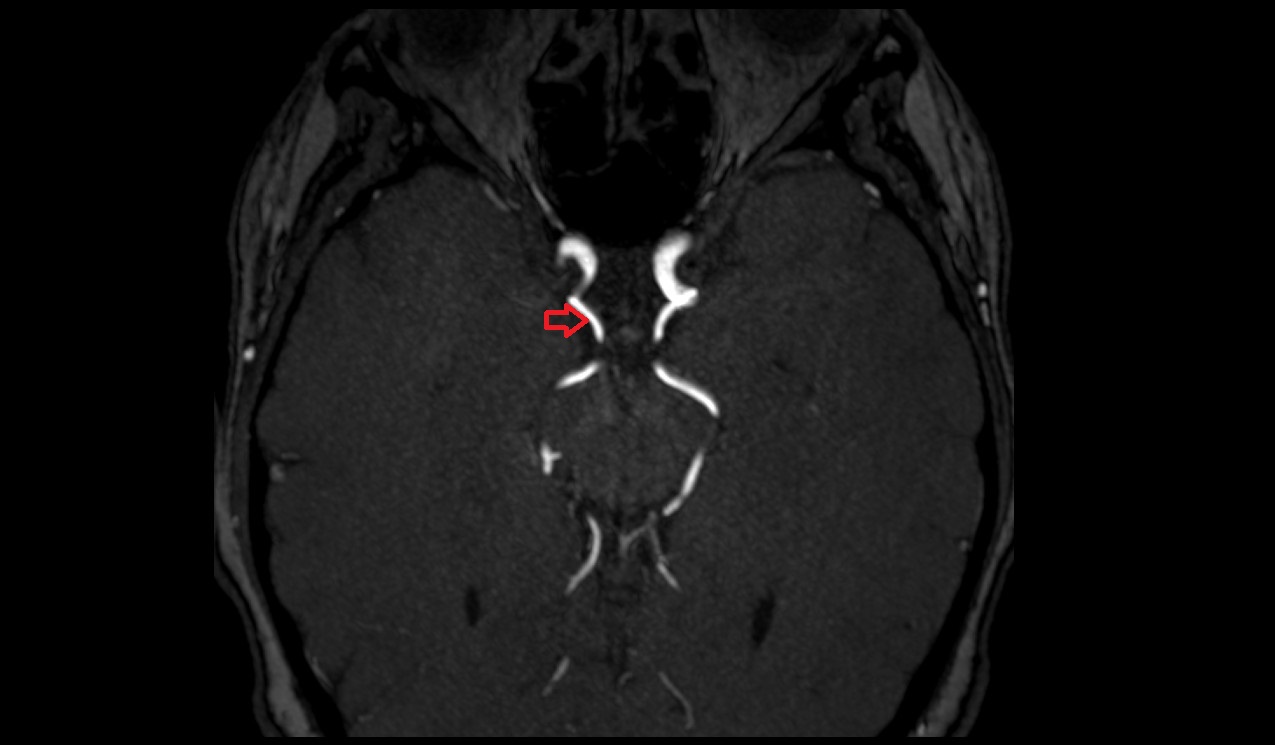

- Anterior cerebral artery (A1 Segment)

- Anterior cerebral artery (A2 Segment)

- Middle cerebral artery horizontal segment (M1)